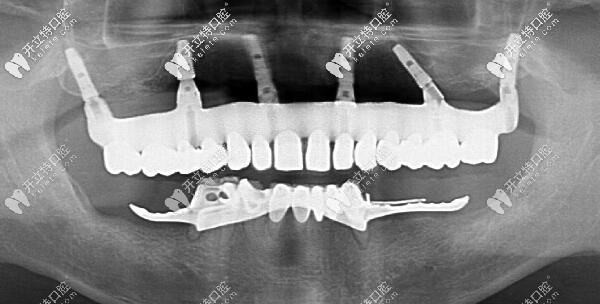

福州維樂(lè)ALL-ON-6上半口即刻種植牙后的CT片

ALL-ON-6上半口即刻種植牙后的CT片▲

劉先生選擇用價(jià)格稍高的瑞典諾貝爾pcc種植體,是因?yàn)榉N植后不容易出現(xiàn)排異、穩(wěn)定性強(qiáng)、使用壽命更長(zhǎng)等優(yōu)勢(shì)~~